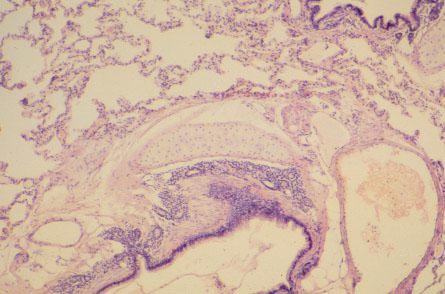

IV-13 (4) Slide 75, Lung (H&E). Medium power view of the cartilage plate.